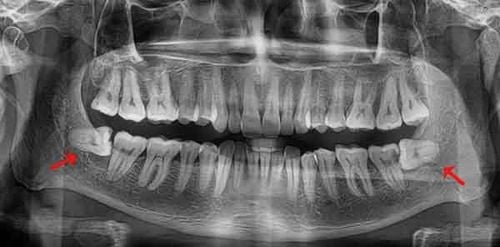

Răng khôn (răng số 8) thường mọc ở vị trí trong cùng của hàm, nơi không còn đủ không gian. Nếu để lâu, răng khôn mọc lệch, mọc ngầm có thể gây ra những hậu quả nghiêm trọng:

• Tiêu xương, sâu răng số 7: Làm hỏng chiếc răng ăn nhai quan trọng nhất bên cạnh.

• U nang xương hàm: Ảnh hưởng đến cấu trúc xương nếu không được can thiệp sớm.

2. Chụp X-quang tại chỗ: Xác định vị trí chân răng và các dây thần kinh xung quanh.